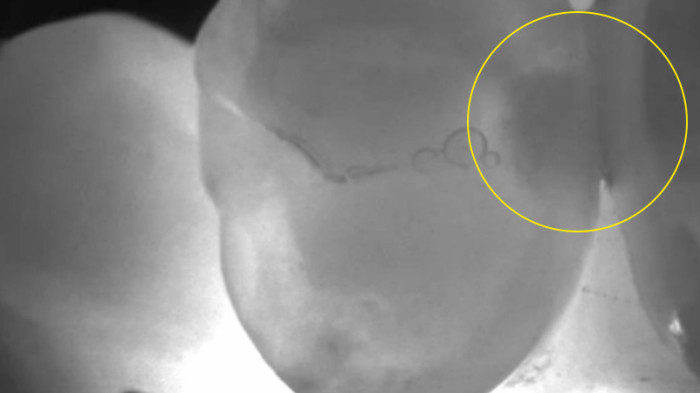

Near-infrared transillumination empowers clinicians to detect proximal lesions that might escape clinical observation and distinguish between lesions confined to the enamel and those that have progressed to the enamel-dentin junction.

Secondary caries

“It is the best method of caries diagnosis, and you can use it safely. […] [regarding] class II cavities and non-cavitated approximal caries, DIAGNOcam has better sensitivity and specificity than bite-wing x-rays [… ] cavity shape is much better explained and visible.”